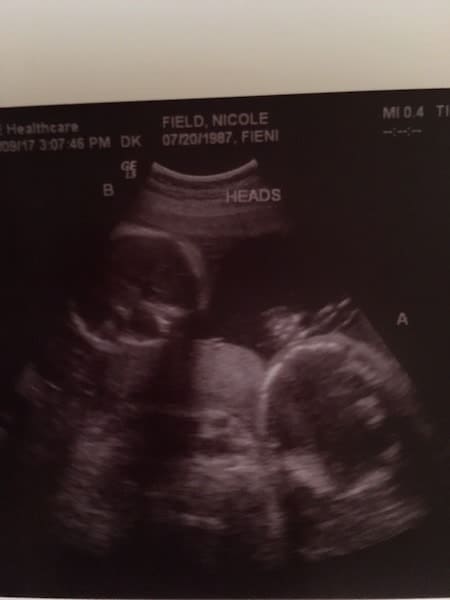

Ultrasound Photos at 21 Weeks Pregnant With Twins